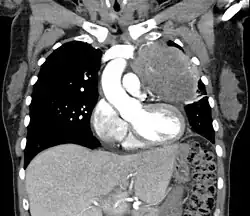

| Thymic carcinoma seen on CT. | |

Diagnosis of thymic carcinoma is based on a combination of clinical, radiologic, and biopsy findings. Most early cases are asymptomatic and found incidentally on chest radiographs as a mass in the anterior mediastinum. Further evaluation consists of additional imaging, such as CT, MRI, and PET, and tumor biopsy, which is the gold standard and provides the definitive diagnosis.[5] Biopsy may be done prior to surgery by fine needle aspiration or during the surgery with concomitant evaluation by the pathologist.[8] Other carcinomas with malignant spread to the thymus are on the differential diagnosis and must be excluded, as they may appear similar to thymic carcinoma on histopathological examination. [3]